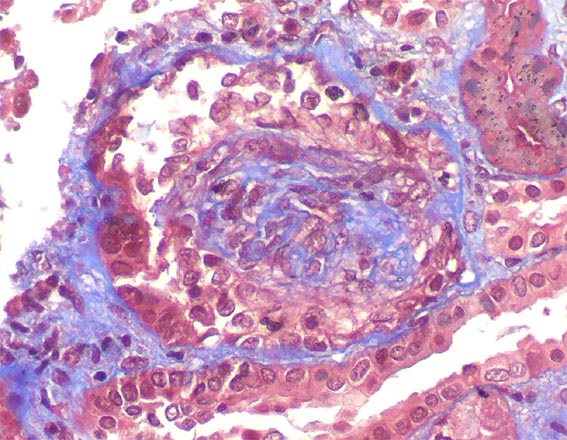

Figure 4.Masson's trichrome stain, X400.